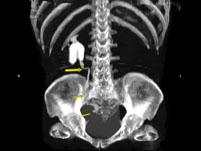

问题 男,55岁,尿频,尿痛伴低热乏力1月。如图所示,下列说法正确的是 ( )

选项 A.左侧输尿管多发性狭窄 B.右侧肾积水 C.膀胱变形 D.左侧输尿管结核 E.左侧输尿管癌

答案 ABCD